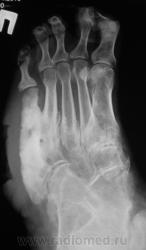

Пациентка направлена на рентгенографию стоп.

Левая стопа.

Возраст - 51 год.

Направительный диагноз - "Диабетическая ангиопатия".

По правой стопе я бы тоже поставил Гарре, но слева такое вылезает. Может все-таки системное?

Хирург, увидев только одну стопу - правую, левая, еще была в работе, ответственно заявил - "остеогенная саркома"...

Системное поражение, возможно как следствие диабетической ангиопатии;слева V плюсневая кость с прерывистым контуром ( возможно остеонекроз на фоне ангиопатии). Не видел подобного ранее.

Картинка вобрала в себя все, что клинически называют "диабетическая стопа". Здесь последствия и ангиопатии, и нейропатии, и присоединившейся инфекции. По-моему, имеется и трофическая язва. Прямо студенческий случай. Хотя, я тоже ранее таких стоп не видел.